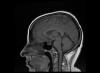

Mujer de 67 años de edad con AP de Fibrilación auricular crónica, Sd depresivo y cirugía gástrica por obesidad mórbida. Acude a consulta de Neurología remitida desde el Servicio de Urgencias por cefalea de reciente...

Neurología: CefaleaEtiología: Anatomía. Variantes de la normalidadDiagnóstico final: Estenosis de acueducto de silvioNivel de certeza: